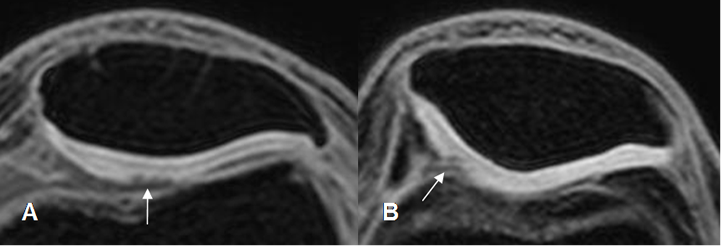

Fig 169. Condromalacia patelar grado 3.

A y B: RM axial en 3D T1 STIR. Pérdida del cartílago articular, mayor del 50%.